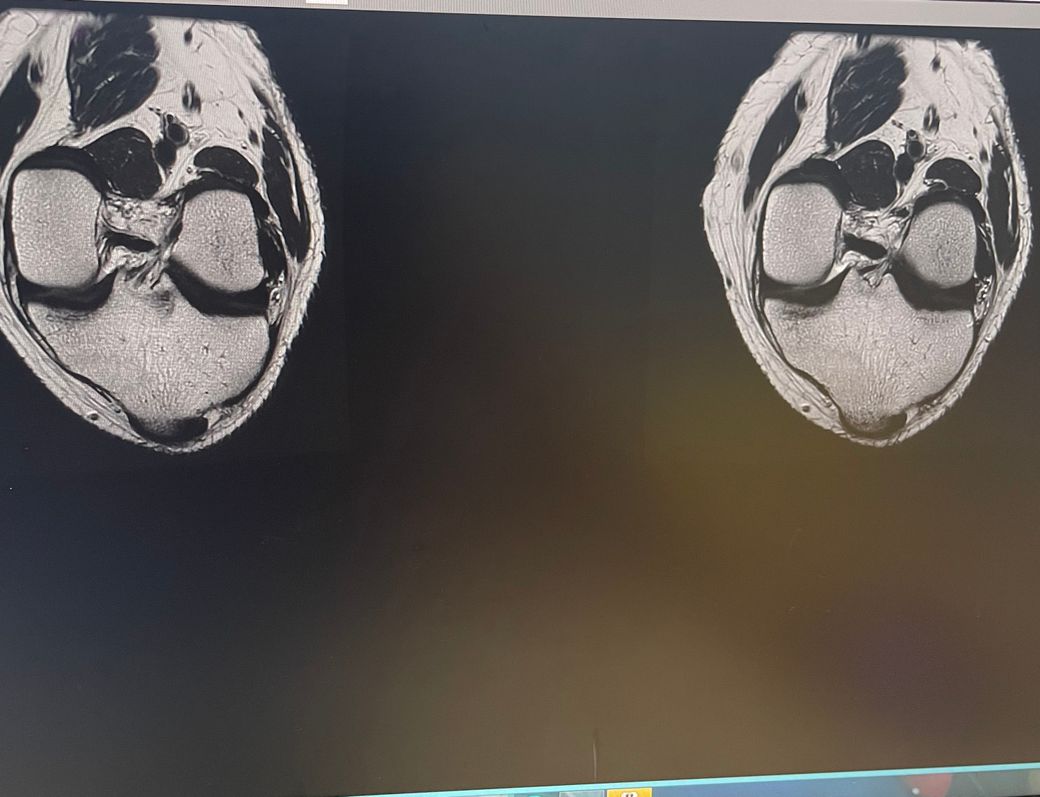

무릎 왼쪽 mri 사진 판독 부탁드리겠습니다.

현재 판독상 인대나 반월연골 손상은 없는 것으로 판독지에 기재되어 있습니다. 임상적인 증상도 중요하니 담당의사와 상의하시고 신검시에 해당과 군의관 판정을 받으시는 것이 좋겠습니다.

십자인대에는 문제가 없지만 반월판의 문제가 있는 것으로 보입니다.

ACL 즉 전방 십자 인대에 불규칙한 소견은 있으나 Tear 즉 십자 인대가 파열되었다는

소견은 관찰되지 않는 상태이며 연골에 퇴행성 변화는 있는 것으로 보이나 이 역시 R/O

으로 확실하지 않음을 의미합니다. 결과적으로 십자 인대의 파열이 명확하지 않는 상태로

군대를 연기할 사유가 될지는 모르며 전방 십자 등 인대 손상의 경우는 명확하게 파열된

소견을 보이지 않는 경우, 군 입대에 문제가 되지는 않을 것으로 생각됩니다.